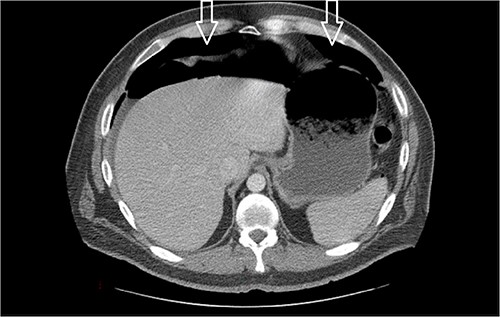

Ten days after discharge, he was readmitted with the same symptoms of nausea and vomiting. The CT showed pneumoperitoneum (see Fig. 2) again with another EL with consequent negative results and no viscus perforations. Lesser amounts of free fluid in both upper quadrants and in the pelvis were noted. These findings remain suspicious for a perforated viscus. Few days later, the patient reported feeling better and was discharged.